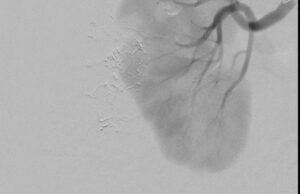

“We are impressed with the GPX embolic,” said Andrew Holden, M.D., MBChB, FRANZCR, EBIR, ONZM, Director of Interventional Radiology, Auckland City Hospital, Auckland, New Zealand. “We delivered GPX through a long 150cm 2.4F microcatheter from the patient’s radial artery. GPX was easy to use, precise, and occluded the tumor well. We look forward to using GPX across a broad range of applications to improve patient care.”

“GPX is easy to prepare, deliver, and control,” said Ryan O’Hara, M.D., Interventional Oncologist, University of Utah, Salt Lake City, Utah USA. “GPX is responsive to the physician and layers well in the vessel during delivery resulting in improved targeting and control. I see potential for this embolic in interventional oncology and other peripheral vascular and neurovascular uses.”